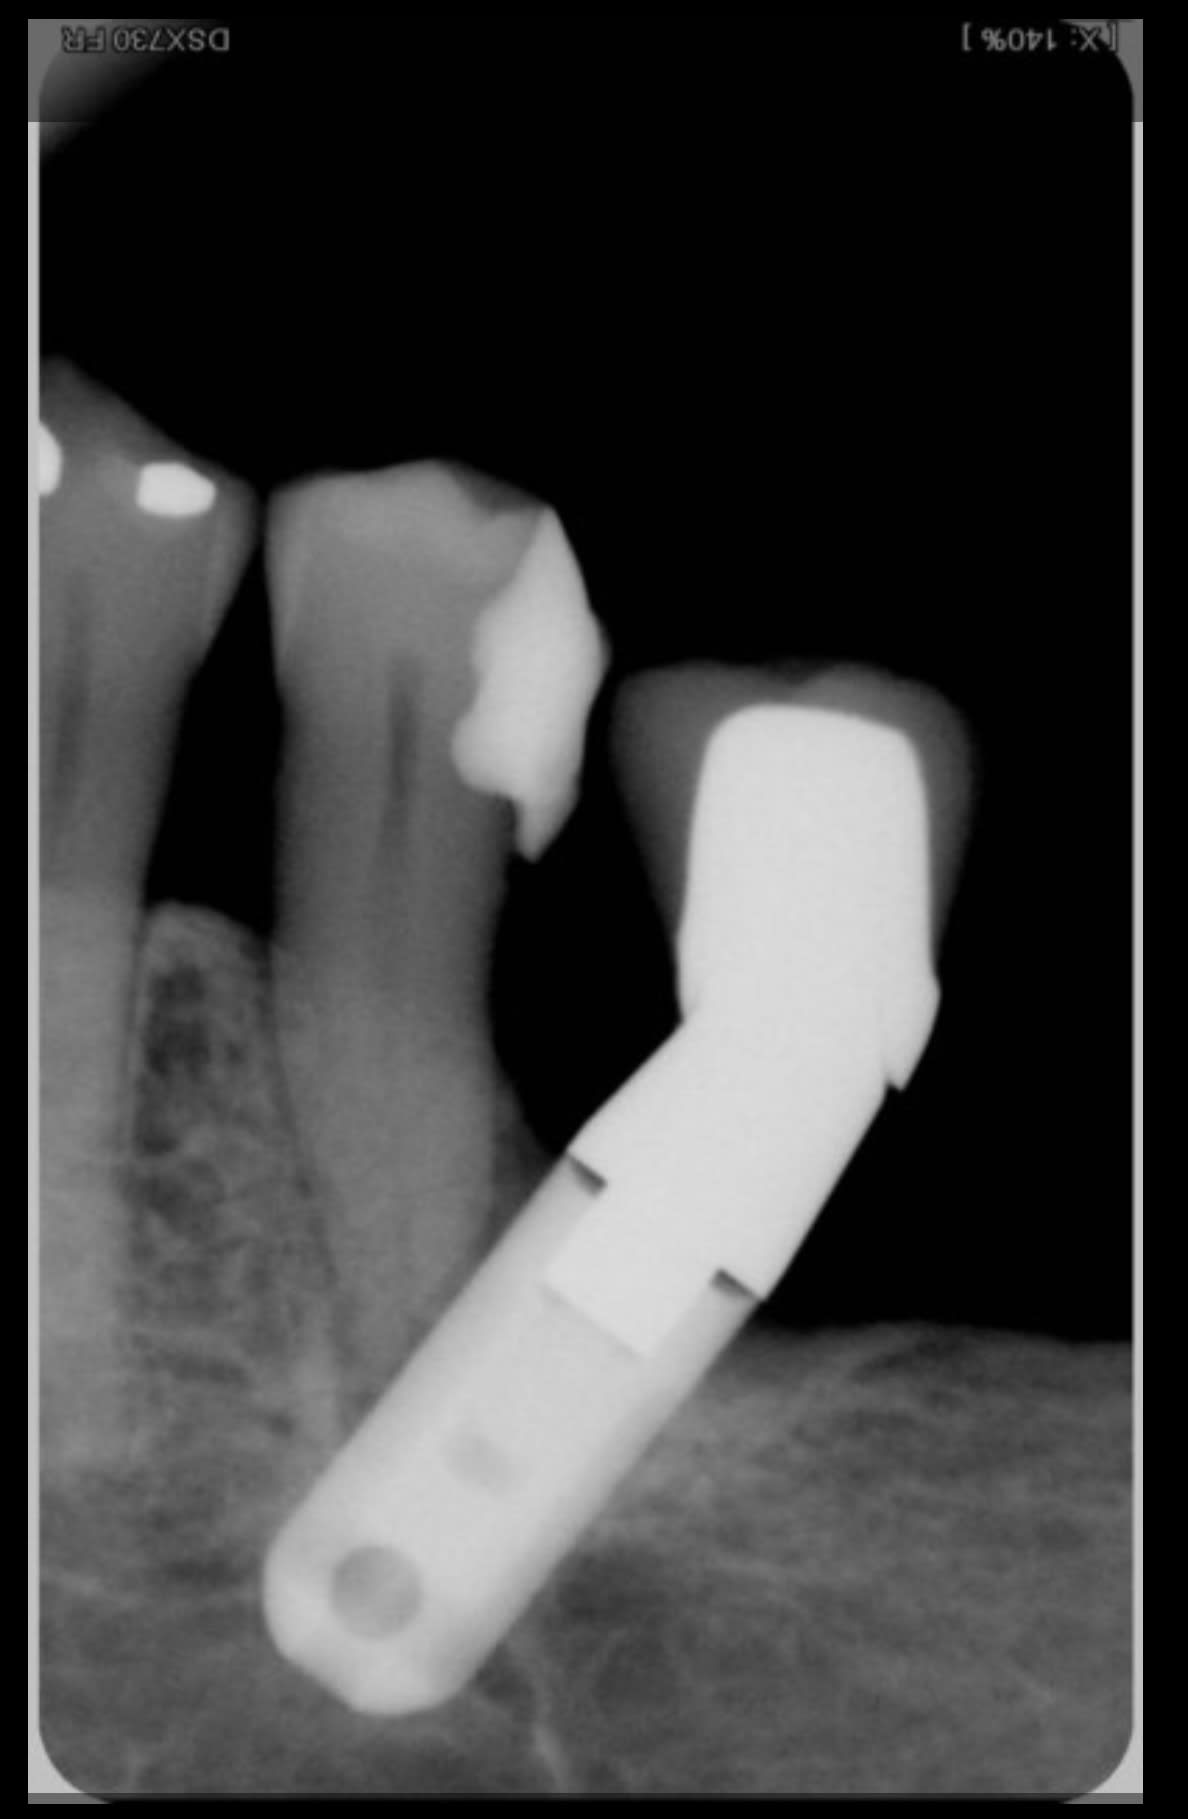

Je crois bien que je viens de visser un 23 dans la racine d'une 22...

- pas de retro de contrôle premier foret en place alors que la 22 à une racine en banane.

Jour de chir. Je lui pose donc une vis ( tiens autre erreur, c'était ma première avec ce système qu'utilise mon associé ).

Le capteur (visiodent ) salle de chir déconne----> pas de foret en place.

Visiblement les forets sont bien taillant, j'ai rien senti.

pose d'un 3.5 11.

-erreur d'axe super classique.

Je t'ai mis la rétro avec le débris de 23 et celle avec le piercing de 22 :)

J'aurais du faire un scan direct après mais il devait aller bosser.

Concernant ce type d'erreurs, voici quelques images trouvé sur Eugenol…

Mais il y a apparemment une erreur de parallaxe, qui elle est systématique! Le seul moyen d'y remédier étant de faire une radio tuteur en place…